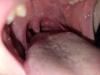

Вы попросите по возможности прям широко рот пусть откроет ребенок, а сами посвятите фонариком прям и загляните, возможно увидите этот желтый гной